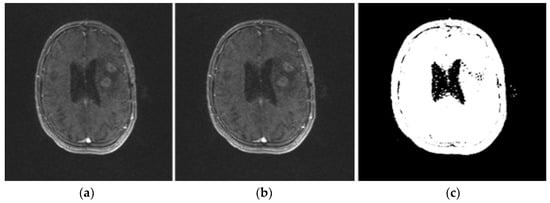

2.2.7. Area Segmentation using Watershed Algorithm

2.2.8. Region Masking and the Separation

2.3. Proposed a Colorized Method for Masked Area Colorization